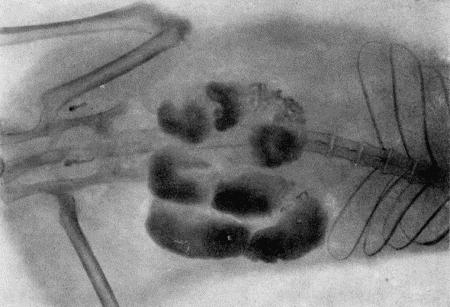

Для более точной диагностики можно использовать рентгенографию после предварительного введения в полость матки контрастной массы (сергозина или сернокислого бария). Вводят одно из этих веществ через тонкий молочный катетер или резиновую трубочку без дополнительного давления (воронкой или шприцем без поршня). Для этого заднюю часть туловища животного приподнимают. Рентгенографией можно определить объем и форму рогов матки (рис. 155).